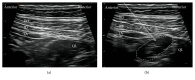

Purpose of Review. Since the original publication on the quadratus lumborum (QL) block, the technique has evolved significantly during the last decade. This review highlights recent advances in various approaches for administering the QL block and proposes directions for future research. Recent Findings. The QL block findings continue to become clearer. We now understand that the QL block has several approach methods (anterior, lateral, posterior, and intramuscular) and the spread of local anesthetic varies with each approach. In particular, dye injected using the anterior QL block approach spread to the L1, L2, and L3 nerve roots and within psoas major and QL muscles. Summary. The QL block is an effective analgesic tool for abdominal surgery. However, the best approach is yet to be determined. Therefore, the anesthetic spread of the several QL blocks must be made clear.